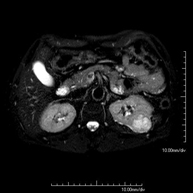

- RM Abdomen

Prueba diagnóstica no invasiva que consiste en la obtención de imágenes de alta definición anatómica del abdomen mediante el empleo de un campo electromagnético y ondas de radio (con un emisor y un receptor). No utiliza radiación ionizante. En esta exploración se incluyen el hígado, páncreas, bazo, vía biliar, vesícula biliar,Entero-RM glándulas suprarrenales, riñones, aorta abdominal, vena cava inferior, estómago, duodeno,…En ocasiones se deberá emplear contraste paramagnético (Gadolinio) para caracterizar las lesiones.